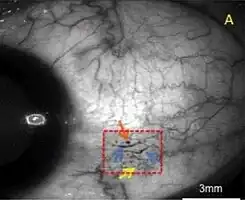

| A case of conjunctival microangiopathy (red dashed-square) secondary to diabetes demonstrating a microaneurysm (orange arrow), vessel dilatation (blue arrows), and vascular tortuosity (yellow arrow). | |